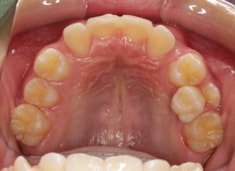

治療法:上顎急速拡大装置+クリアスナップ+フェイスマスク+上顎3番は開窓牽引CT写真にて位置確認

(難症例のため、小児期の矯正を2段階に設定しました)

骨年齢は実年齢よりも低めなので、今後下顎の旺盛な成長が見込まれます。